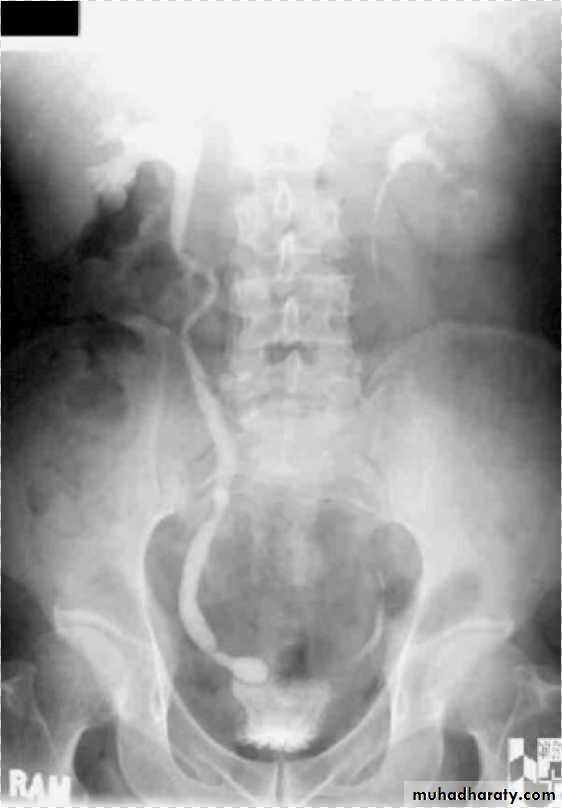

Horse shoe kidney -Kidneys may fail to separate.

-Almost invariably the lower poles remain fused.

-The kidneys axes are more parallel to the spine and malrotated.

-Diagnosis can be made by plain x-ray in some cases.

IVU shows

1. The kidneys at low position .

2.Close to the spine with long axis parallel to the spine .

3. Malrotation manifested by medially directed calyces.

4- The renal pelvis and ureters are anterior and lateral in position .